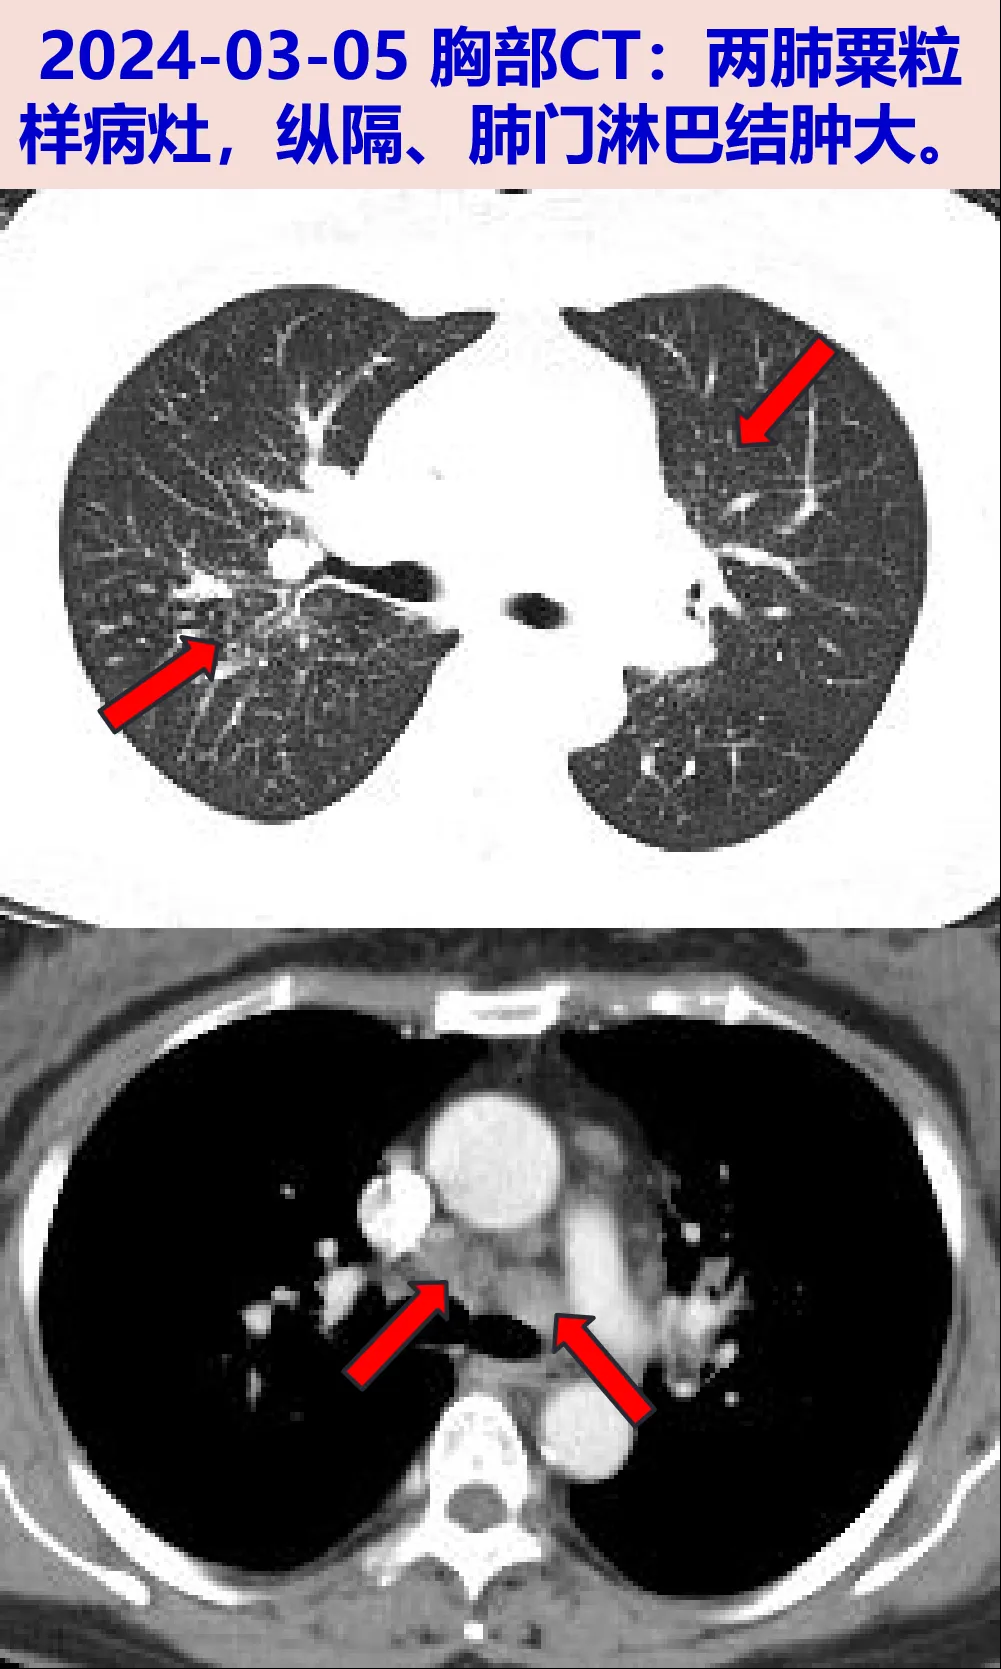

2024-03-05 胸部CT:右肺中叶节段实变不张,两肺多发结节(多发粟粒样改变),两肺慢性炎症,两肺门及纵隔、两侧颈根部-锁骨区多发肿大淋巴结;血常规:WBC 5.88×10^9/L,N 54.9%。无发热盗汗消瘦、咳嗽咳痰、呼吸困难、胸痛等。

结节病:患者中年女性,结节病史10年,既往CT表现为双侧肺门、纵隔多发淋巴结肿大,本次CT新增肺内多发粟粒样病灶,从“一元论”角度考虑,可符合结节病表现,考虑疾病进展,可进一步经气管镜行病理及病原学检查明确诊断。

2024-03-07 行全麻支气管镜:左固有上叶支气管粘膜肿胀,尖段管腔可见重度狭窄,远端不能窥见;右中叶支气管粘膜肿胀,管腔狭窄,远端不能窥见,于右中叶行灌洗。中央超声探及多个4R组淋巴结,互相融合,直径约1.59cm,探及4L组淋巴结直径约1.14cm,分别行TBNA。